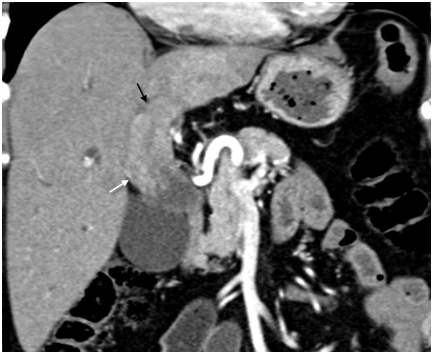

Figure 6 Atrophy (white arrow) and differential enhancement (black arrow) of the left lobe due to portal vein involvement in type IIIb hilar cholangiocarcinoma.

Portal vein involvement was subcategorized as involvement of the main vein, left branch, right branch, and anterior and posterior division of right branch (Figure 5). In 91(75.83%) patients, the portal vein was involved (Table 5A & Table 5B). In 27 out of 32 patients of type IIIa, portal vein was involved. Ipsilateral(right side) branch involvement was seen in 24 cases whereas contralateral branch involvement was seen in two cases and main branch involvement was seen in one case without right branch invasion. In 32 out of 39 patients of type IIIb, left branch was involved and in two cases right branch was involved without left branch invasion. In type IV, invasion of main portal vein or it’s right or left branch, or all three were seen in 24 patients. Two patients of type I and only four patients of type II showed portal venous invasion. Portal vein involvement was present in 70(74.46%) patients, 20(86.95%) patients, and 1(33.33%) patient in periductal-infiltrating, mass-forming, and intraductal-growing tumor respectively. Either main hepatic artery or its branches were involved in 57(47.50%) cases. Inferior vena cava was found to be involved in six (05.00%) cases and hepatic veins were involved in 12(10.00%) cases. Out of 91 patients with portal vein involvement, differential enhancement of the lobes was seen in 44(48.35%) patients (Figure 6).

Liver parenchymal involvement adjacent to the mass lesion was present in 60(50.00%) patients (Figure 5). Liver invasion was present in 39(41.48%) patients, and 21(91.30%) patients in periductal-infiltrating and mass-forming tumor respectively. None of the patient of intraductal-growing tumor showed liver invasion. Seventy five(62.50%) patients had atrophy of the lobe, out of which 45(60.00%) patients had left lobe atrophy and 30(40.00%) patients had right lobe atrophy(either anterior or posterior segment or both). Lobar atrophy was present in one(33.33%), three(23.07%), 24(75.00%), 29(74.35%), and 18(54.54%) patients in Bismuth-Corlette type I, II, IIIa, IIIb, and IV respectively (Figure 6). Lobar atrophy was present in 56(59.57%) patients, 18(78.26%) patients, and 1(3.33%) patient in periductal-infiltrating, mass-forming, and intraductal-growing tumor respectively.